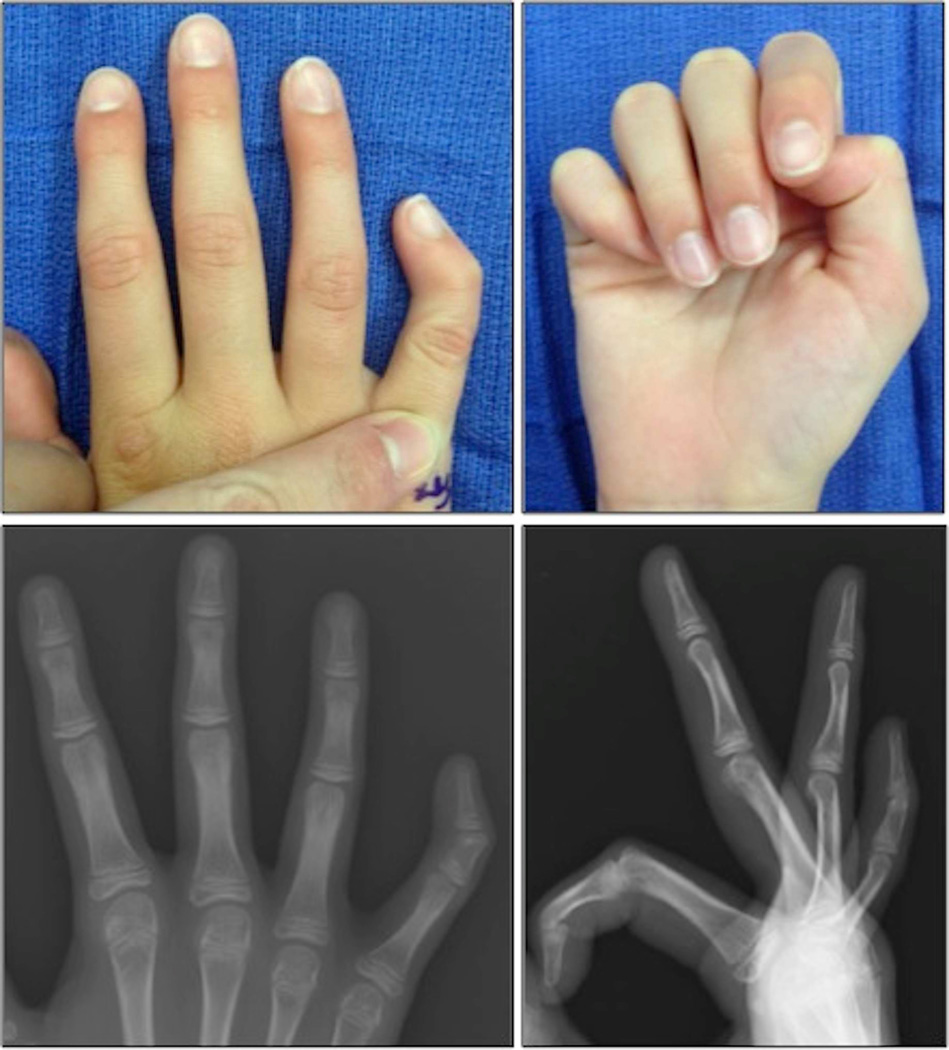

Xray of extremities revealed hypoplasia and wedgeshaped deformity of... Download Scientific What Is A Wedge Deformity When vertebrae collapse, they form a wedge shape, which makes the spine bend forward. The fracture forms on the front of the vertebra. There are three types of compression fractures: Wedge fractures cause the front of a vertebra to compress, leading to spinal deformity. Bracing helps to reduce acute pain by immobilizing the fracture. Wedge fracture — this fracture usually. What Is A Wedge Deformity.

of Opening Wedge Osteotomy to Correct Angular Deformity in Clinodactyly Journal of What Is A Wedge Deformity Wedge fracture — this fracture usually occurs in the front of the vertebra, collapsing the bone in. The broken bone collapses and takes on a wedge shape. Vertebral wedge fractures are the most common osteoporosis fracture type. There are three types of compression fractures: The name wedge fracture, refers to the wedge. The fracture forms on the front of the. What Is A Wedge Deformity.

Figure 1 from of opening wedge osteotomy to correct angular deformity in little finger What Is A Wedge Deformity It also helps to reduce the eventual loss in height and in. When vertebrae collapse, they form a wedge shape, which makes the spine bend forward. Wedge fractures cause the front of a vertebra to compress, leading to spinal deformity. Bracing helps to reduce acute pain by immobilizing the fracture. Indications would include severe fracture with neurologic injury, severe angulation,. What Is A Wedge Deformity.

From www.semanticscholar.org

Figure 2 from of opening wedge osteotomy to correct angular deformity in little finger What Is A Wedge Deformity The broken bone collapses and takes on a wedge shape. Wedge fractures cause the front of a vertebra to compress, leading to spinal deformity. When vertebrae collapse, they form a wedge shape, which makes the spine bend forward. The name wedge fracture, refers to the wedge. The fracture forms on the front of the vertebra. Indications would include severe fracture. What Is A Wedge Deformity.